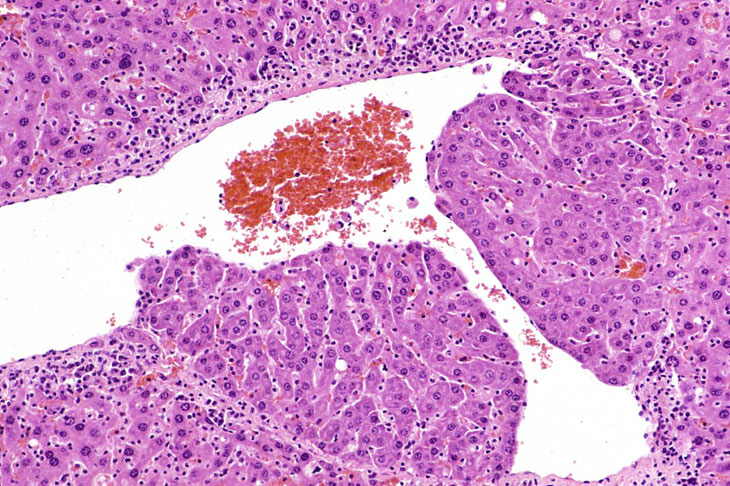

In some foci of cellular alteration, primarily basophilic foci, hepatocytes may occasional be seen to protrude into the lumen of hepatic veins. They are usually lined by a layer of flattened endothelial cells. This change has been considered by some to represent a form of microinvasion and such lesions have been diagnosed as hepatocellular carcinomas, possibly motivated by the fact that most are seen within foci induced by treatment with hepatocarcinogens. However, similar changes are occasionally seen in untreated mice and may not necessarily be associated with a focus of cellular alteration. Consequently, we cannot be certain that this change is actually a microcarcinoma. Two clusters of hepatocytes protruding into a large hepatic vein.

Another example of protrusion of hepatocytes into an hepatic vein.